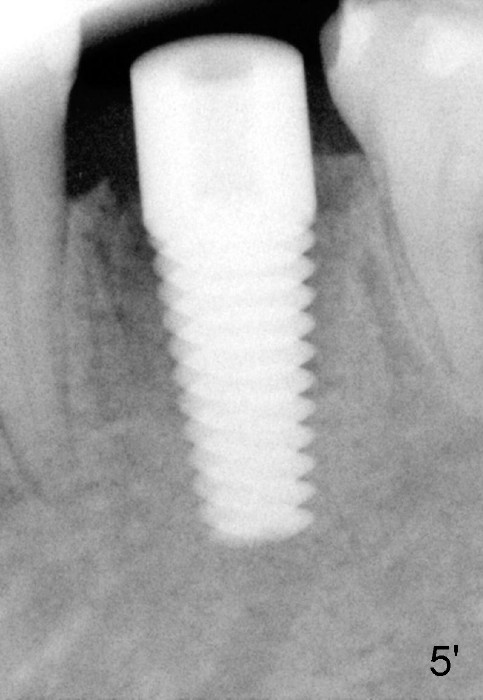

Fig.5: A 6x17 mm implant is placed.